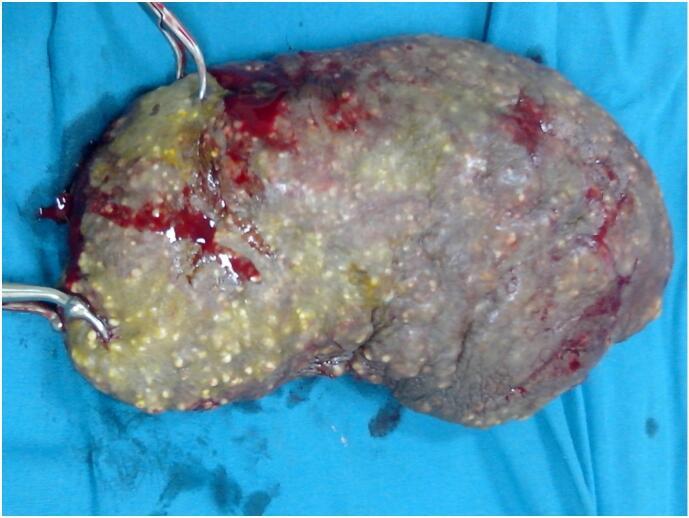

A 47-year-old man with a 15-year history of painless, chamois-colored nodules on his scrotum. Surgical excision of the affected skin was performed, followed by primary closure, with histopathological examination confirming ISC. The patient recovered well with no recurrence noted at a 14-month follow-up.

一名47岁男性,阴囊出现无痛性、羚羊皮色结节已有15年。对受影响的皮肤进行了手术切除,随后进行一期缝合,组织病理学检查确诊为ISC。患者恢复良好,在14个月的随访中未发现复发。